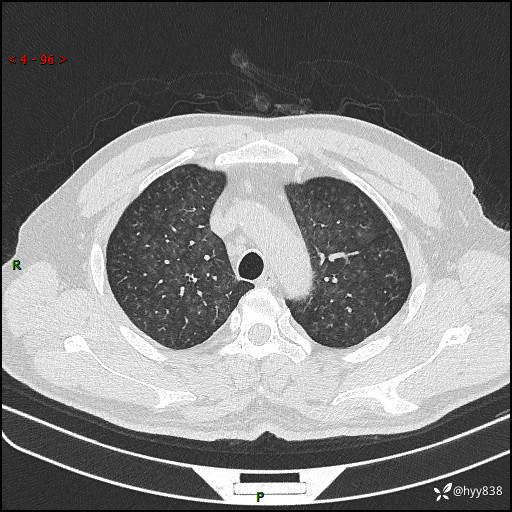

昨天肺结节门诊,“对门”呼吸科申请会诊病例,弥漫性肺部病变---结果公布~

患者年龄:51岁

主诉:发热、咳嗽、咳痰1周

简要病史:患者1周前无明显诱因出现咽喉部疼痛,随后出现咳嗽咳痰,起初干咳为主,后出现咳少许绿色痰,当时有发热,体温为39℃,无畏寒寒战,无胸闷胸痛,无活动后气短,无咯血,无鼻塞流涕,无全身酸痛,患者于诊所输液治疗后体温正常,但仍有咳嗽。患者3天前当地县人民医院就诊,患者仍有咳嗽,咳嗽较为频繁,咳嗽后出现头痛,伴有少许咳痰,随后出现活动后气短,1天前患者再次出现发热,体温最高为40℃,伴有畏寒寒战,伴有乏力、纳差,伴有胸闷不适,无咯血,无全身皮疹,无血尿、尿频尿急尿痛,无腹泻,诊断为“重症肺炎 感染性休克 肾功能异常 痛风”;予以抗感染(亚胺培南),抗病毒(奥司他韦)等对症治疗。患者复查胸部CT提示双肺病灶较前有所增多,建议上级医院就诊,门诊以“肺部感染”收入我科。 起病以来,患者食欲欠佳,大小便正常,睡眠、精神欠佳,体力下降、体重无明显变化。

辅助检查:CT

临床诊断:肺部感染

胸部HRCT